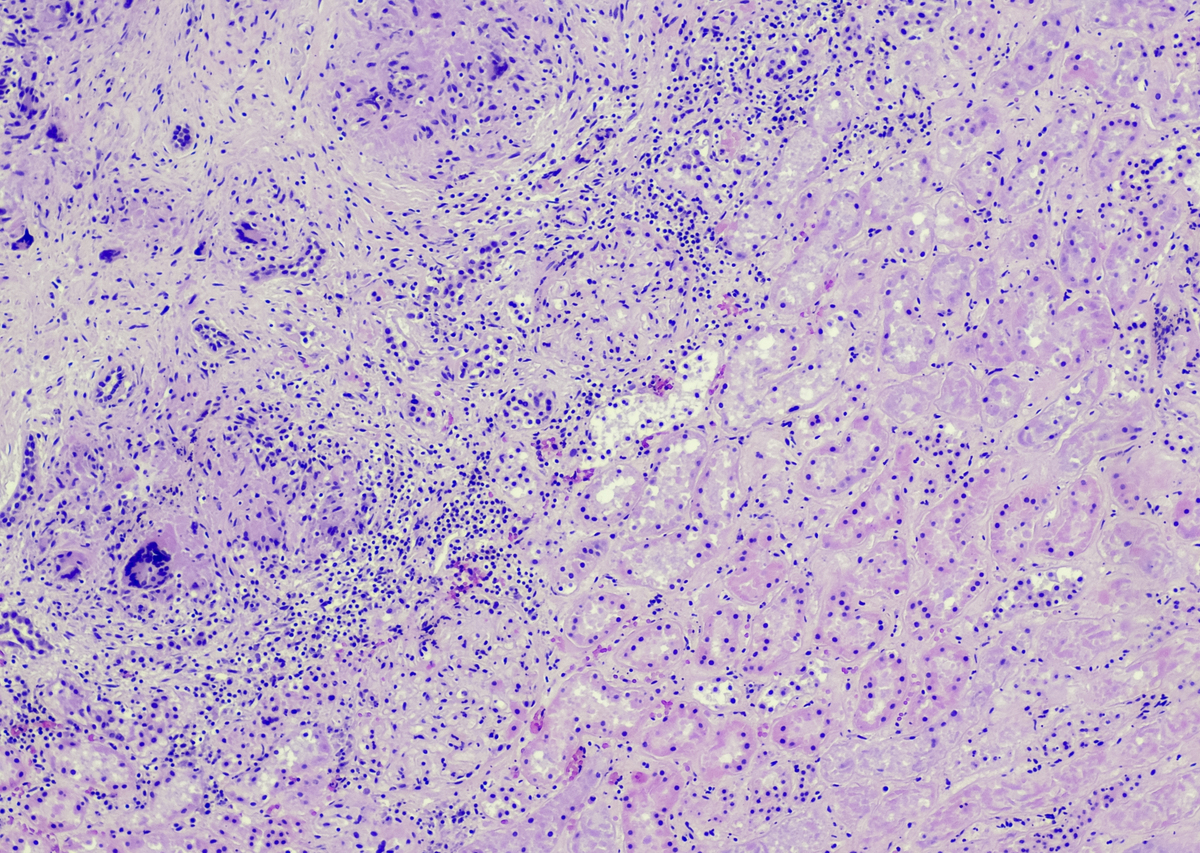

Primary human endometrial epithelial and stromal cells were successfully isolated using a previously described procedure with minor modifications.